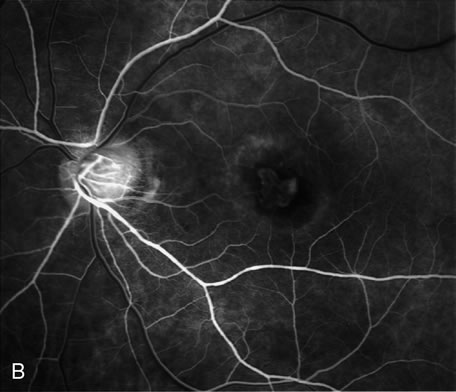

Fig. 18. A. Late-phase fluorescein angiogram demonstrates the presence of actively leaking, subfoveal, classic choroidal neovascularization. B. After photodynamic treatment (PDT) with Visudyne there was complete closure of the neovascular membrane. The round, hypofluorescence corresponds to the area treated with PDT. There was no damage to the retinal vasculature.

FA is needed to assess response to laser photocoagulation of a CNV and to diagnose recurrent membranes.51,54 The authors generally obtain angiograms 2 weeks, 1 month, 3 months, and 6 months after treatment. The risk of recurrence is greatest during the first 3 months, and the patient, who often has decreased vision due to prior neurosensory detachment, may be asymptomatic. FA is also needed to evaluate the results of PDT. In the original protocol of the Verteporfin in Photodynamic Therapy (VIP) and Treatment of Age-Related Macular Degeneration with Photodynamic Therapy (TAP) studies, a fluorescein angiogram was obtained every 3 months, and if there was persistent leakage from the CNV PDT was applied again (see Fig. 1820).60